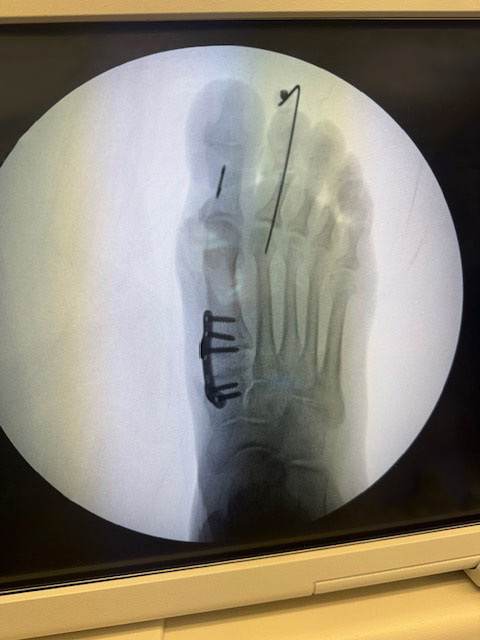

"Surgical misadventure" by another surgeon about 8 years ago. The wrong fixation was used for a flatfoot repair, & the deformity was not corrected. Patient came in with severe foot & ankle pain, with no arch at all. She was unable to play with her grandchild because the pain was so bad, & because she felt unsteady. The old hardware was removed, a lateral calcaneal lengthening osteotomy was performed along with a medial column/1st ray realignment. The ankle was painfully arthritic, & patient elected a total ankle replacement vs. an ankle fusion. She is now able to walk pain free & play with her grandchildren!